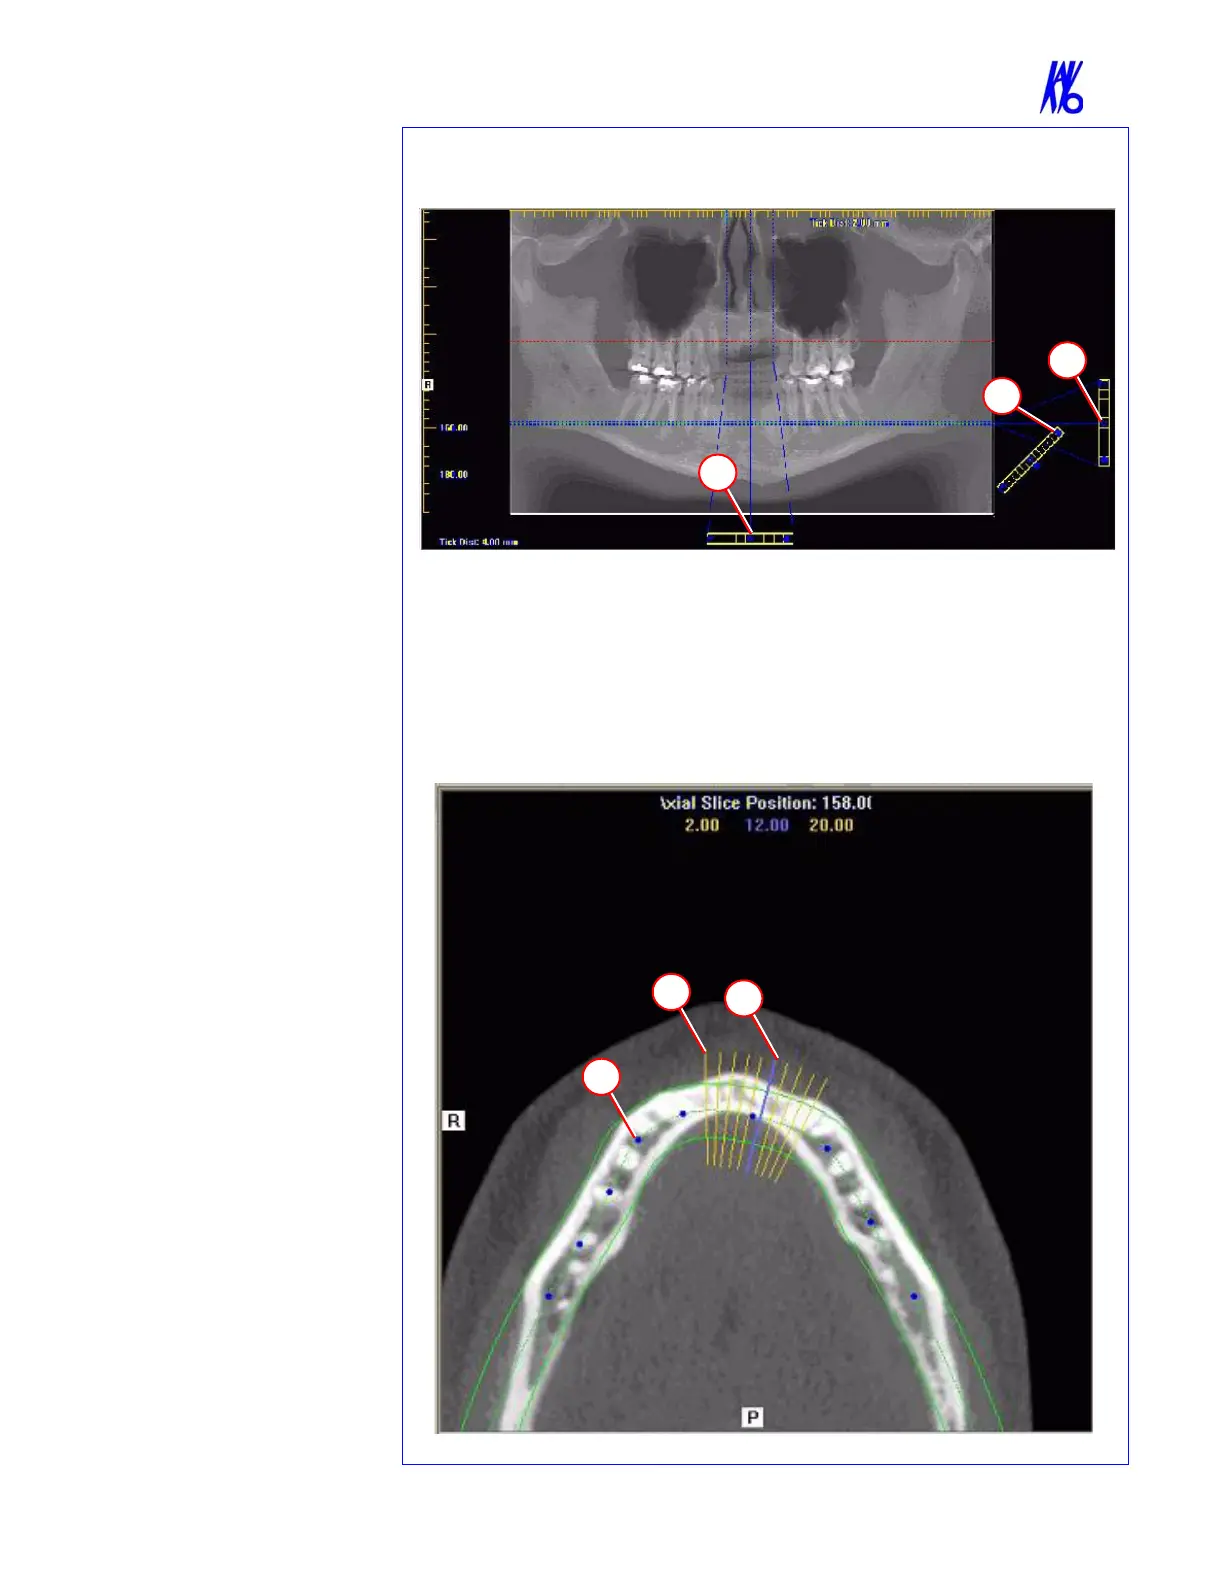

PAN TOOLS

1. Horizontal Tool Bar

Drag this center tool left to right

to move the slice location of the

Cross Sections. The center slice

is outlined in Blue on the Cross

Sections.

Drag the tool to the right to

adjust the slice thickness of the

Cross Sections.

2. Diagonal Tool Bar

Drag this tool to adjust slice

thickness of Panoramic View.

Drag the center tool to adjust

Pan Focal Trough.

Click the bottom tool to change

the Pan view from

Radiographic to MIP.

3. Vertical Tool Bar

Drag this center tool up or

down to adjust height of

anatomy viewed in the Cross

Sections and Axial.

AXIAL TOOLS

1. Drag blue dots to adjust Pan

Map.

2. Orange hash marks are Slice

Location Indicators.

3. Blue hash mark represents the

centerline of the axial slices

displayed on the Cross Section

views.

Panoramic Map

Axial Slice Position

3

2

1